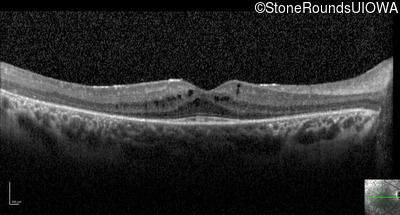

Optical Coherence Tomography - Right - 20/40

Exemplar / OCT Stack